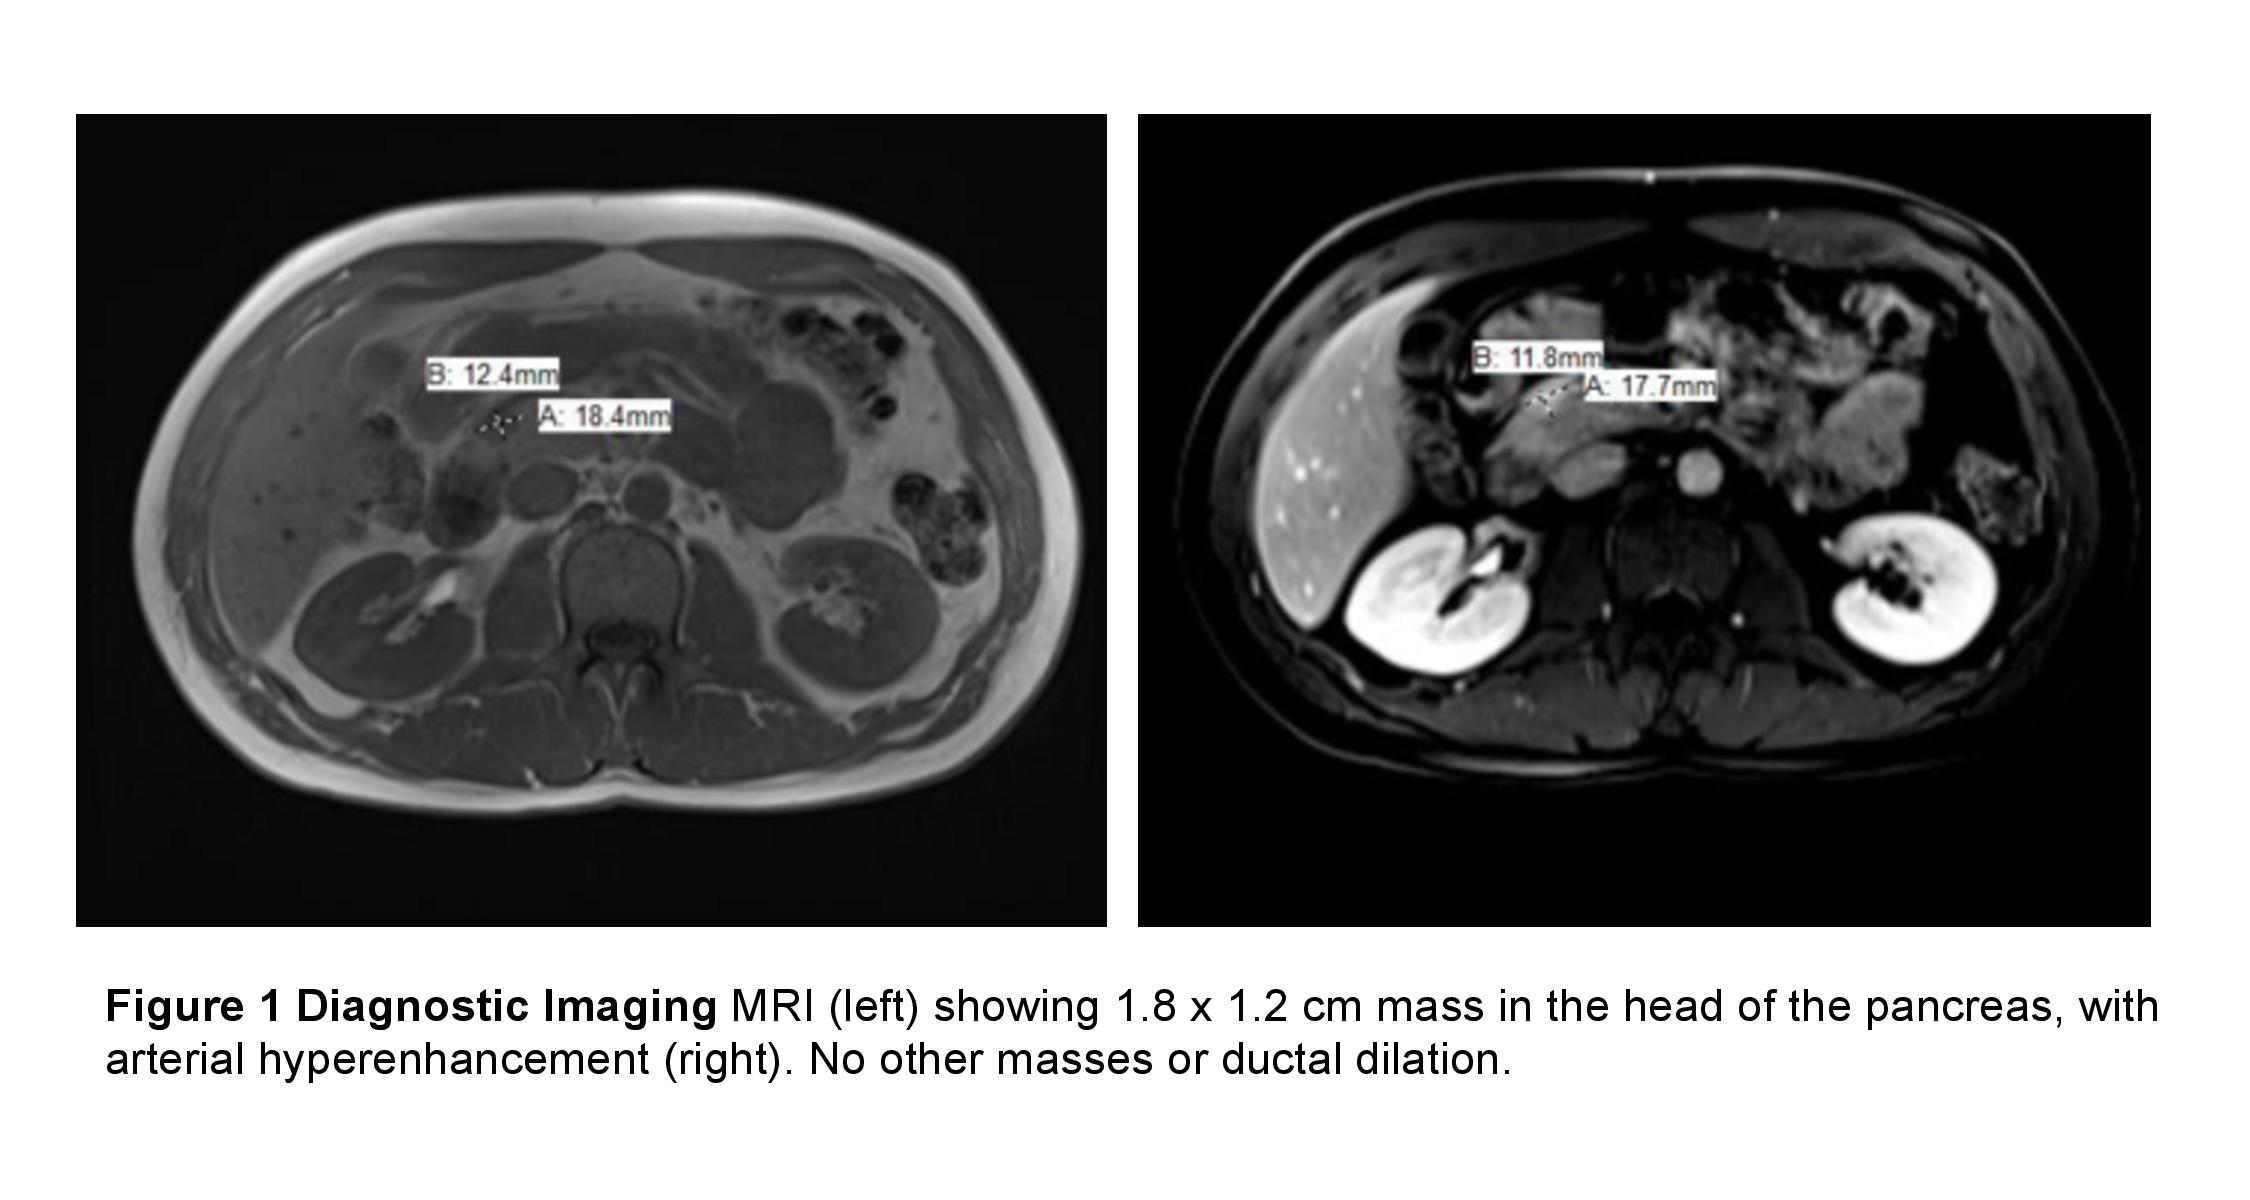

Case Presentation: A 33-year-old male with no significant past medical history was admitted after being found unconscious at his desk with a blood glucose of 28 mg/dL. The patient reported multiple episodes of confusion, slurred speech, and unsteady gait in the context of fasting that was relieved with meals. He also reported almost a decade of high sugar intake – consuming 1.5L of soda and multiple candy bars daily – to prevent lightheadedness. He denied any medication or drug use. On admission, the patient was hemodynamically stable with an unremarkable physical exam. Laboratory values were significant for a glucose of 156 mg/dL. After a 5-hour fast, he had a glucose of 34 mg/dL. Further work-up revealed insulin of 21 uIU/mL, c-peptide of 2.4 ng/mL (RR 0.8- 3.5), B-hydroxybutyric acid <0.2 mmol/L, and a hemoglobin A1c of 4.3%. He had a negative sulfonylurea panel, insulin antibody, toxicology screen, and ethanol level as well as normal thyroid stimulating hormone, liver function tests, complete blood count, and a borderline-normal ACTH stimulation test. Magnetic resonance imaging revealed a hyper-enhancing mass in the head of the pancreas. The patient underwent local resection and enucleation of the mass; pathology confirmed an insulinoma.

The next step in diagnosis is localization of the tumor with computed tomography, magnetic resonance imaging, or endoscopic ultrasound, which has the highest sensitivity and specificity for insulinoma. If these imaging modalities fail, a selective arterial calcium stimulation test can aid in localization. The majority of insulinomas are benign and optimal treatment includes surgical resection.